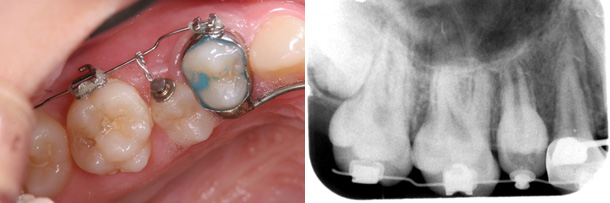

症例:埋まったままで自然に萌出できない歯を牽引し、咬み合わせを改善

主訴:上の歯がなかなか出てこない

診断:上顎右側第二小臼歯の埋伏

年齢:11歳

装置:上顎部分的ブラケット装置、上顎リンガルアーチ

治療期間:3か月

抜歯:なし

費用:50,000円+税

矯正前

矯正後